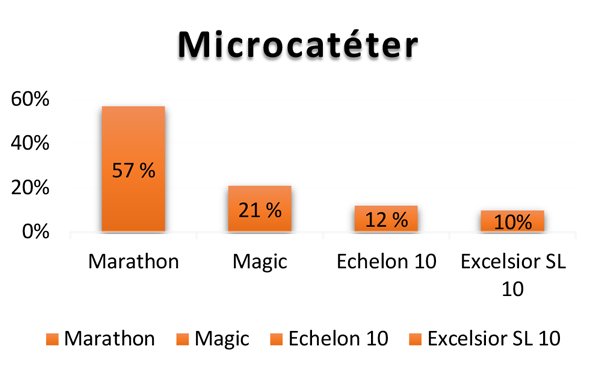

Se utilizó un abordaje femoral 3 F en 83% de los casos, con mayor prevalencia en pacientes menores de 15 meses (fig. 2). Se emplearon microcatéteres Marathon® 1.5 y Magic® 1.5 y 1.2 en el 78% de las sesiones. Tiempo de fluoroscopía en primera sesión entre 0:41 y 4:13 min en tumores unilaterales, 1:12 y 7:34 en bilaterales. Uno de los objetivos de esta técnica es disminuir al máximo las dosis de radiación ionizante entregada al paciente ya que es un tumor radiosensible. Para ello utilizamos fluoroscopia en dosis mínima, nos apoyamos en el road-mapping y en la radioscopía simple, y realizamos adquisiciones con sustracción digital únicamente para documentar el nivel de opacificación coroidea en única proyección lateral monoplanar.

Bajo anestesia general. Heparinización 50 o 70 UI/kg dependiendo si es un procedimiento uni o bilateral respectivamente. Por introductor femoral 3 F se navega un microcatéter (Marathon® 1.5, Magic® 1.5/1.2, Echelon 10® en orden de elección) con microguía (Mirage®, Hybrid® 0,008”, Syncro® 10) hasta la arteria carótida interna (Fig 3).

Fig. 3: Microcatéteres más utilizados y en orden de preferencia.